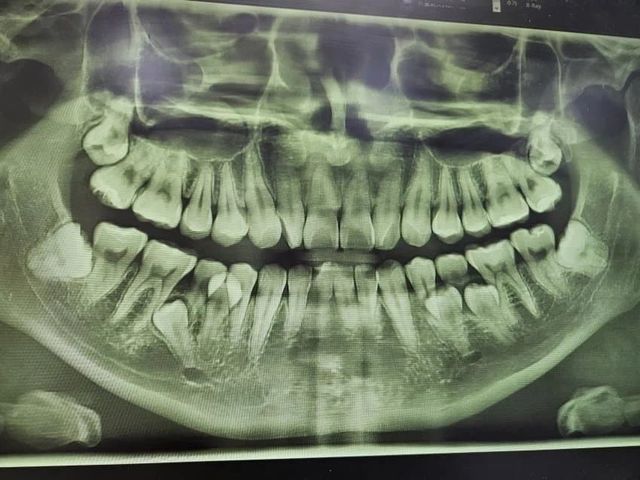

사랑니 8개

오늘 수술 한다고 함